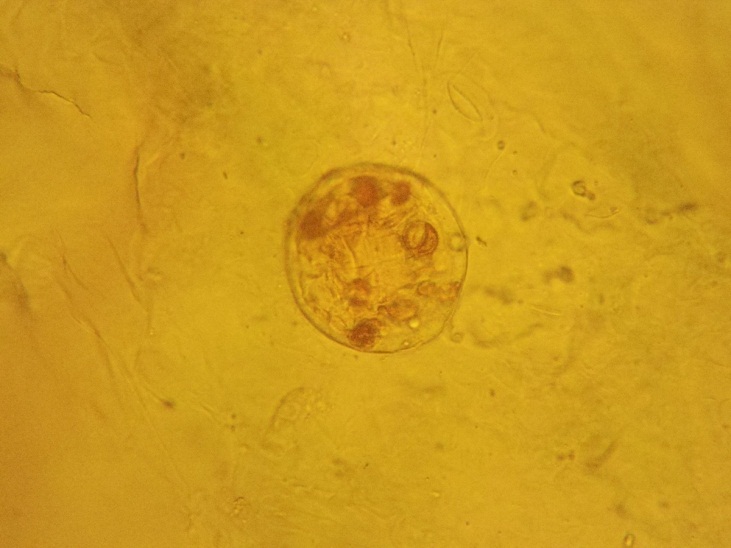

При микроскопическом исследовании препаратов листа с поверхности обнаруживаются простые многоклеточные волоски с бородавчатой кутикулой и головчатые волоски с одноклеточной ножкой и обратнояйцевидной одноклеточной головкой. Устьица диацитные. По поверхности в углублениях видны многочисленные эфирномасличные железки (рис.4). Эпидермис извилистостенный (рис.3). [1]

Рис.4. Эфирномасличная железка

- На основе проведенного микроскопического анализа были обнаружены диагностические признаки Мяты перечной (извилистые клетки эпидермиса, эфирномасличные вместилища) и Мелиссы лекарственной (клетки эпидермиса c извилистыми стенками, устьица аномоцитного типа, железистые волоски).